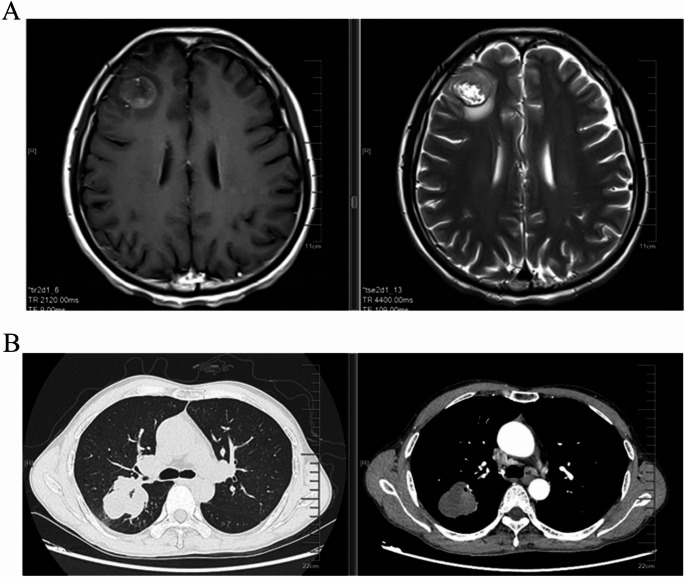

背景:smarca4缺陷未分化胸椎肿瘤(SMARCA4-UT)是一种罕见的高侵袭性恶性肿瘤,其特点是早期远处转移,预后差,中位总生存期(OS)仅为4-7个月。传统的治疗方法提供有限的益处,而新的数据表明联合免疫治疗、化疗和抗血管生成方法的疗效。我们报告一例52岁男性重度吸烟史,表现为意识丧失和肢体抽搐。影像学显示脑转移和胸部肿瘤。在手术切除脑病变和肺活检后,患者被诊断为SMARCA4-UT,无可靶向的驱动突变和程序性死亡-配体1 (PD-L1)肿瘤比例评分(TPS)结论:综合化疗免疫治疗、抗血管生成、巩固放疗和挽救性手术的多模式治疗可使SMARCA4-UT脑转移患者持久生存。它强调了结合全身和局部治疗的潜力,为管理这种具有挑战性的疾病提供了有价值的见解。

Background: SMARCA4-deficient undifferentiated thoracic tumor (SMARCA4-UT) is a rare and highly aggressive malignancy characterized by early distant metastasis and a poor prognosis, with a median overall survival (OS) of only 4-7 months. Traditional therapies offer limited benefit, while emerging data suggest the efficacy of combined immunotherapy, chemotherapy, and anti-angiogenic approaches. We report a case of a 52-year-old male with a heavy smoking history who presented with loss of consciousness and limb convulsions. Imaging revealed brain metastasis and a thoracic tumor. After surgical removal of the brain lesion and a lung biopsy, the patient was diagnosed with SMARCA4-UT, showing no targetable driver mutations and a programmed death-ligand 1 (PD-L1) tumor proportion score (TPS) < 1%. The patient underwent first-line treatment with tislelizumab, bevacizumab, carboplatin, and paclitaxel. Despite discontinuation of bevacizumab due to a tumor cavity, the patient achieved partial remission (PR) after six cycles. Notably, consolidative thoracic radiotherapy (TRT) was administered following systemic disease control to enhance local control. After 5 months of maintenance therapy, oligoprogression of the primary lung lesion was detected and the progression-free survival (PFS) of first-line treatment reached 14 months. The patient then performed salvage surgery for local lesion and continued with maintenance treatment. As of May 2025, the patient has survived for 31 months since the initial diagnosis.